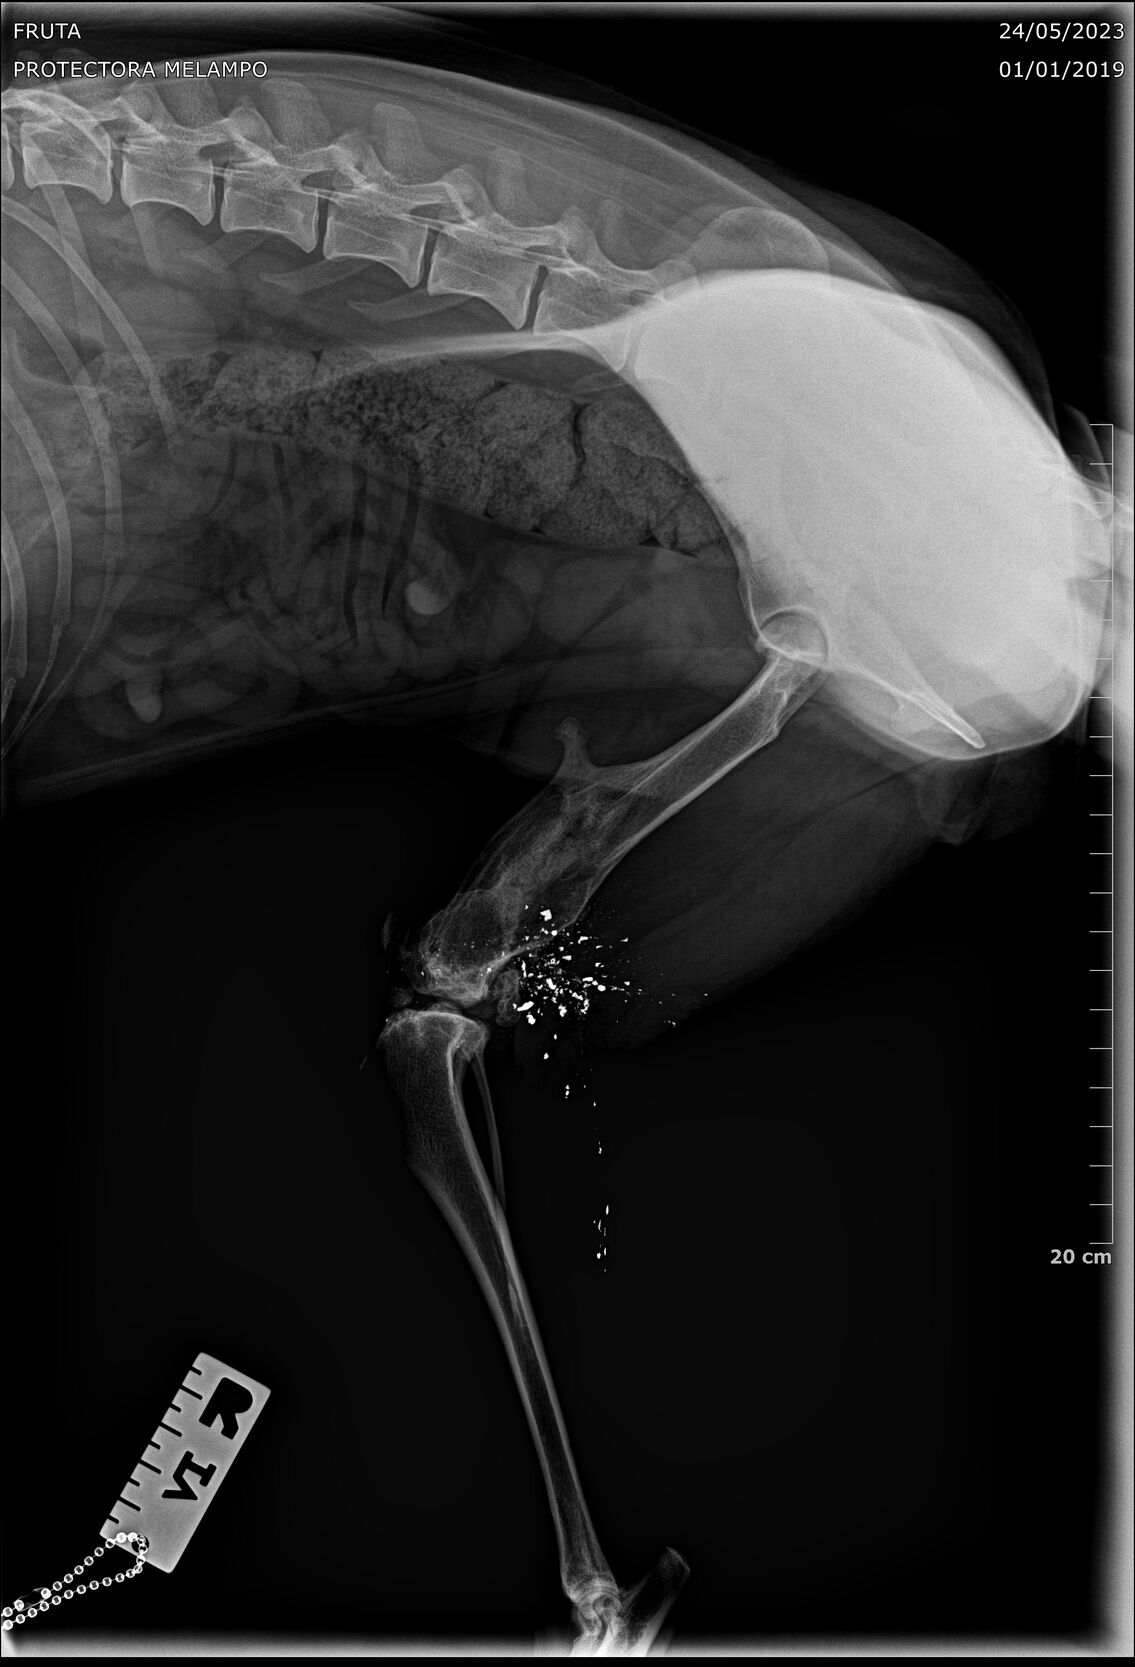

Fruta wurde kastriert und ihr alte Verletzung wurde dabei auch gleich geröngt. Dabei kam heraus, dass Fruta eine Schussverletzung hat und immer noch Schrot im Bein hat. Die Röntgenbilder sind weiter unten zu finden.

Fruta’s Hinterbein wurde beim Spezialisten abgeklärt. Das Bein ist steif, sie hat aber keine Schmerzen. Es stört sie auch nicht, sie läuft, rennt und hüpft auch ohne Probleme aufs Sofa.